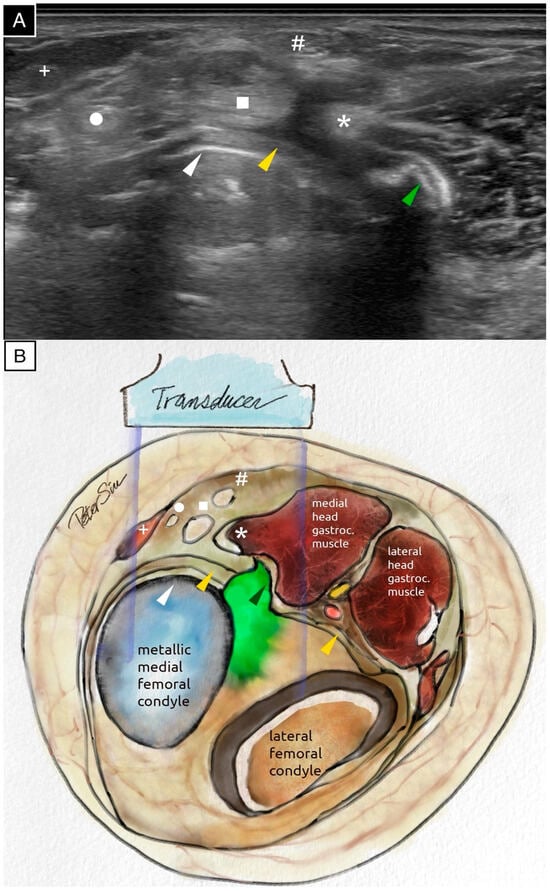

Figure 2.

The transverse ultrasound scan (A) and the schematic illustration (B) of the posteromedial knee demonstrate extruded cement positioned posterior to the metallic femoral component. The extruded cement impinges on the posterior capsule and the medial head of the gastrocnemius muscle. The surface of the extruded cement reflects ultrasound waves, producing a surface echogenic line and casting a strong posterior acoustic shadow. The following anatomical structures are labeled: the extruded cement (green arrowhead), the posterior capsule (yellow arrowhead), the posterior border of the metallic femoral component (white arrowhead), the medial head of the gastrocnemius muscle (asterisk), the semimembranosus tendon (square), the gracilis tendon (circle), the semitendinosus tendon (hash sign), and the sartorius tendon (plus sign). The ultrasound image, acquired using the Fujifilm Sonosite PX with an L15-4 linear probe (operating at the general frequency setting, with the dynamic range set to 0 on a scale from −3 to +3, and the time gain compensation kept at the factory setting with no adjustments), provided a detailed assessment of the surrounding soft tissues and highlighted the extensive application of ultrasound technology in the medical field []. An ultrasound evaluation is provided in Video S1.